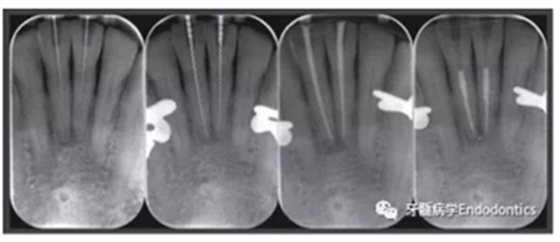

在患者下頜牙上試戴導(dǎo)板(帶有專門制作的金屬袖,steco-system-technik GmbH & Co. KG, Hamburg, Germany) ,判斷是否合適(圖7)。通過導(dǎo)板可以定位根管入路點(diǎn),并微創(chuàng)去除牙釉質(zhì),直到牙本質(zhì)暴露。鉆針轉(zhuǎn)速設(shè)定為10000RPM,上下提拉鉆頭獲得根管根尖1/3的入路(圖8)。當(dāng)鉆針柄接觸導(dǎo)板上的金屬袖時(shí),鉆針尖端到達(dá)目標(biāo)位點(diǎn)。整個(gè)根尖入路的制備過程耗時(shí)約10分鐘。圖9展示了微創(chuàng)預(yù)備的根管入路。然后進(jìn)行常規(guī)的根管治療。用1%的次氯酸鈉沖洗根管,單支往返銼(R25, VDW, Munich, Germany)預(yù)備根管,超聲蕩洗,干燥根管后用氫氧化鈣(Ultracal XS, Ultradent Products Inc, South Jordan, UT, USA) 封藥,暫封(CavitTM, 3 M ESPE) 。兩周后,患牙均無叩痛,使用熱牙膠垂直加壓技術(shù)和環(huán)氧樹脂糊劑(AH Plus, De Trey, Konstanz, Germany)充填根管。圖10為根管治療過程中拍攝的x線片。髓腔清理后,使用復(fù)合樹脂(Filtek Supreme XTE, 3 M ESPE, Seefeld,Germany) 和多步法粘接劑(Optibond FL, Kerr, Orange, CA, USA).充填。

圖10.根管治療過程中拍攝的X線片。(a)微創(chuàng)根管入路制備完成拍攝的定位片,(b)根管長度測(cè)量,(c)試主尖片,(d)去除冠方根充填物后的最終根充效果。